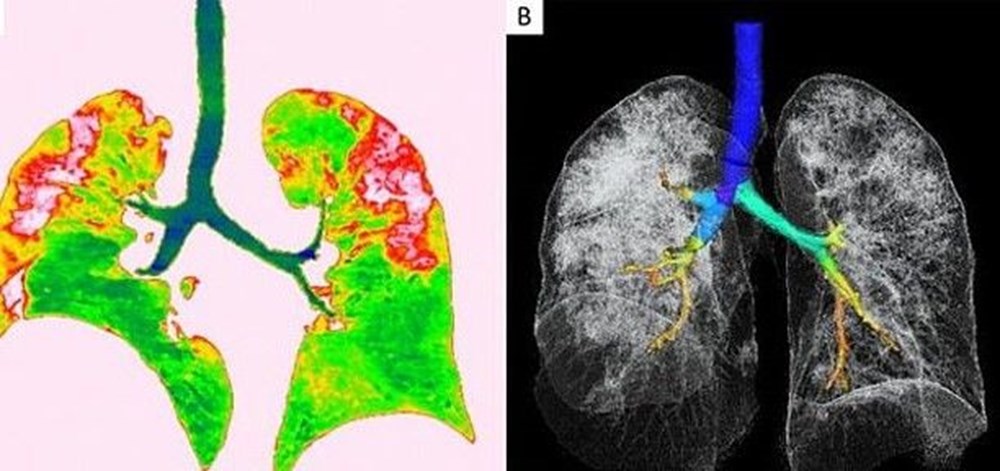

Solda yer alan fotoğrafta kırmızı olarak görülen alanlarda nodüller, sağ tarafta ise akciğer ve trakeanın üç boyutlu görüntüsü yer alıyor. Beyaz alanlarda koronavirüsün tahribi görülüyor.

Japonya'dan döndükten sonra koronavirüse yakalan Çin'in Sichuan eyaletinden 45 yaşındaki bir kadının taramalarında ise, virüsün akciğerinin sol üst lobunda ters hale edilmiş hale işareti oluşturdu.